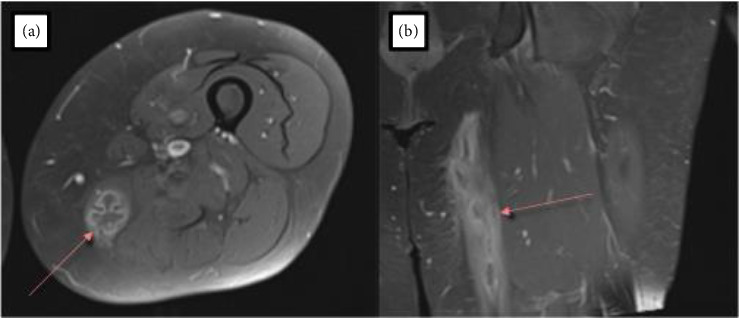

Mycobacterium abscessus is a rapidly growing non-tuberculous Mycobacterium (NTM) primarily associated with pulmonary infections, particularly in individuals with underlying lung conditions. While soft tissue infections are less common, their incidence has been increasing. These infections are challenging to treat due to inherent resistance to many antibiotics obtained through spontaneous mutation as well as physical characteristics of the microbes. The case presented here describes a 61-year-old female without obvious risk factors for mycobacterial infection who developed an intramuscular abscess over a 2-year period following a mechanical fall. Surgical resection with a complex antibiotic regimen was required based on macrolide resistance and a lack of established treatment plans for such a rare presentation. This case highlights the increasing incidence of NTM and the variable clinical presentation. Early identification with a combination of surgery and antibiotics is usually indicated to successfully manage these infections. Even without obvious risk factors, NTM infection should be considered in the presence of soft tissue and intramuscular abscesses.